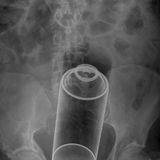

Diese Dinge gehören dort eigentlich nicht hin: Immer wieder passieren Unfälle, wenn Menschen sich zur sexuellen Stimulation über den After Gegenstände in den Darm einführen. Ob Orangen, Spraydosen oder Kaffeebüchsen - der Fantasie sind dabei offenbar keine Grenzen gesetzt.

Die Webseite radiopaedia.org zeigt, welche Dinge Ärzte auf Röntgenbildern schon entdeckt haben. Die Aufnahmen wirken skurril und erschreckend zugleich und machen deutlich, wie weit die eingeführten Dinge bereits in den mescnhlichen Darm vordringen können.

Aber Glück im Unglück für die Patienten: Die Gegenstände können meist ohne Operation entfernt werden. Sehen Sie hier einige der spektakulärsten Röntgenaufnahmen. Da runzeln selbst Chirurgen die Stirn.